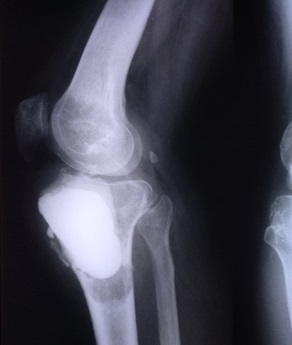

Children and adults with tumors and tumor-like disorders of the bone and soft tissue, such as bone metastases, sarcomas, benign and malignant tumors of the bone or soft tissue, and pathologic fractures, are treated by the Division of Orthopaedic Oncology, which provides them with the highest quality care.

Orthopedic oncology, also known as Musculoskeletal Oncology, focuses on the diagnosis and treatment of both benign and malignant bone tumors, along with other unusual lesions affecting the musculoskeletal system. Bone cancer and soft tissue sarcomas, though rare, demand a comprehensive, multidisciplinary approach to diagnosis and treatment.